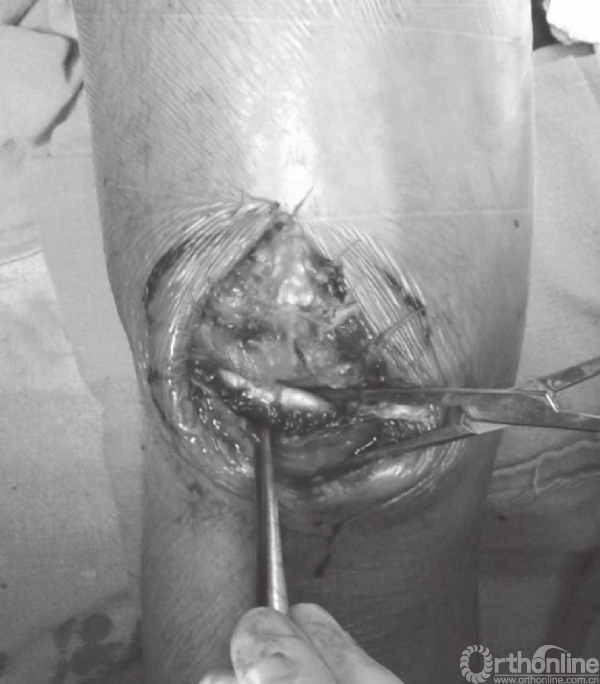

应仔细探查关节,以辨识游离骨块以及关节面损伤(图6)。此时,可对骨折进行复位,并以复位钳进行临时固定。检查骨折复位情况以及关节稳定性,关节内骨块的解剖复位是非常重要的。术中复位困难,可能是因为小骨块或者软组织嵌于骨折端。

图6 应仔细探查关节以辨识游离骨块以及关节面损伤